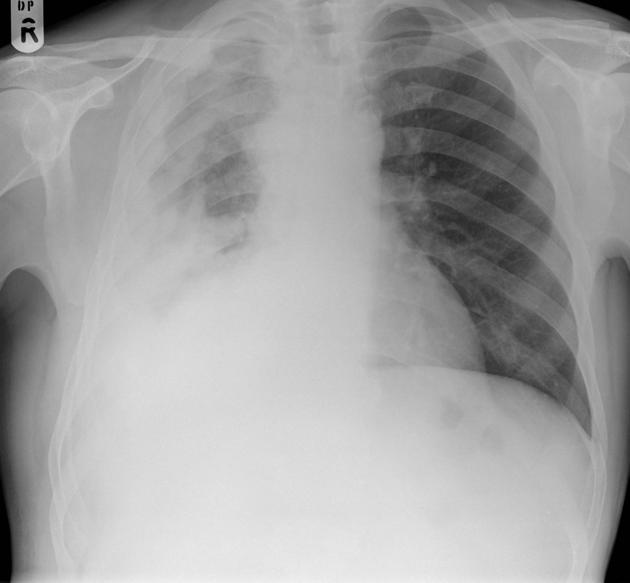

CLINICAL HISTORY:

32yo Female

Dyspnoea

FINDINGS:

Bilateral reticulonodular shadowing with diffuse cystic changes.

Lung volumes are preserved.

No pleural abnormalities demonstrated.

Heart size is normal.

Hila and mediastinal contours are normal.

IMPRESSION:

Lymphangioleiomyomatosis